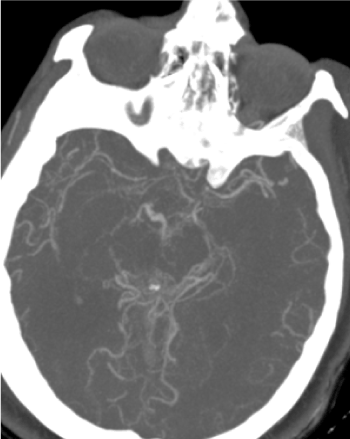

CT brain which reveals bilateral diffuse subarachnoid hemorrhage and dilated ventricles (Figure 1). CT cerebral angiography reveals no aneurysms associated with diffuse narrowing of supraclinoid portions of both internal carotid arteries (Figure 2). Diagnostic angiography of right internal carotid artery reveals diffuse narrowing of the supra-clinoid portion (Figure 3). Diagnostic angiography of left internal carotid artery reveals diffuse narrowing of the supra-clinoid portion with multiple collaterals (Figure 4). Diagnostic angiography reveals multiple meningeal collaterals (Figure 5).

Figure 2.Axial cut of CTA reveals no aneurysms associated with diffuse narrowing of supraclinoid portions of both internal carotid arteries associated with basal collaterals